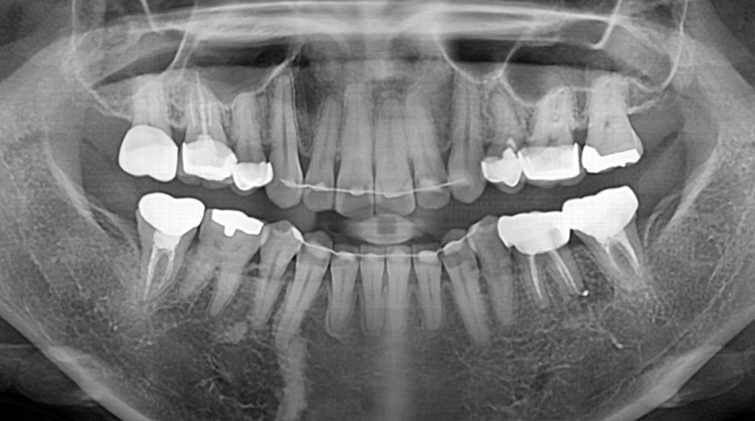

발치 즉시 임플란트.

After